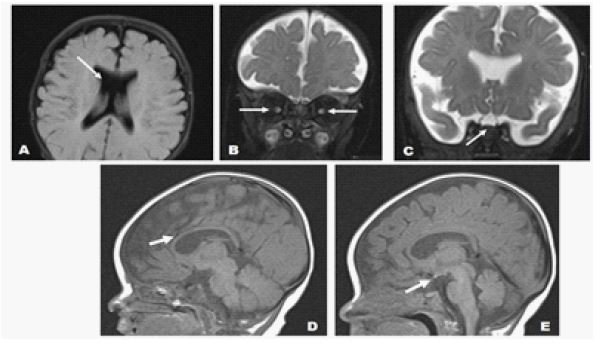

A 53-day-old female infant was referred to our hospital with complaints of rotatory nystagmus and prolonged jaundice. The prenatal period was uneventful, and the mother had no systemic illnesses during pregnancy. Delivery occurred spontaneously at 40+5 weeks of gestation, with a birth weight of 3700 g. On postnatal day 1, the infant developed hypoglycemia and was monitored in the neonatal intensive care unit for 11 days. Following discharge, she attended regular outpatient follow-ups. On examination, the infant appeared icteric, exhibited poor eye tracking, and demonstrated searching nystagmus. Neurological evaluation revealed normal muscle tone. A 2/6 systolic murmur was detected on cardiovascular examination, while other systemic evaluations were within normal limits. Laboratory investigations revealed the following results: total bilirubin: 11.8 mg/dL, direct bilirubin: 0.62 mg/dL. Given the suspicion of hypopituitarism, hormonal analysis was performed, showing free T4: 0.71 ng/dL (low), TSH: 6 ìIU/mL (mildly elevated), ACTH: 24.9 pg/mL (normal), cortisol: 0.75 ìg/dL (low), and prolactin: 91.1 ng/mL (elevated). Echocardiography identified a small apical muscular Ventricular Septal Defect (VSD) and a 2 mm Atrial Septal Defect (ASD) with left-to-right shunting. Ophthalmological examination revealed optic nerve hypoplasia, which was considered the primary cause of the visual impairment. Transfontanel ultrasound showed a corpus callosum thickness of 2 mm, suggestive of hypoplasia. The septum pellucidum was absent, and a single ventricle anomaly was noted. Cranial Magnetic Resonance Imaging (MRI) findings included bilateral optic nerve and optic chiasm hypoplasia, absence of the septum pellucidum, and an ectopic neurohypophysis, Supporting the Diagnosis of SOD (Figure 1). To investigate potential genetic etiologies, Whole Exome Sequencing (WES) was performed on the patient’s blood sample. Comprehensive analysis of known SOD-associated genes (e.g., HESX1, SOX2, OTX2, SOX3) and other relevant neurodevelopmental genes did not identify any pathogenic or likely pathogenic variants. This finding indicates a lack of identifiable genetic correlation with known mutations in this particular case. Based on clinical, laboratory, and radiological evaluations, the patient was diagnosed with septo-optic dysplasia, and a multidisciplinary follow-up plan was established. Endocrinological support therapy was initiated due to hypopituitarism, and the patient was closely monitored for growth hormone deficiency, adrenal insufficiency, and other endocrine dysfunctions. The family was thoroughly informed about the risk of vision loss associated with optic nerve hypoplasia, and appropriate interventions were recommended to support visual development.

Figure 1: Non-contrast MRI of the brain on a 1.5T scanner shows (A) Absence of the septum pellucidum; (B) Bilateral optic nerve hypoplasia in the intraorbital segments; (C) Optic chiasm agenesis in the suprasellar region; (D) Thin corpus callosum, and (E) T1 hyperintense focus suggestive of the neurohypophysis is observed in the posterior pituitary within the sellar region, the T1 hyperintensity related to the neurohypophysis is ectopically located superiorly (white arrows).